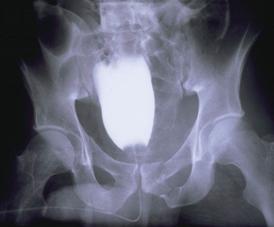

Fracturi pelviene multiple Fracturi bilaterale de ramuri pubiene

Compresie bilaterala Aspect CT Disjunctie sacro-iliaca stanga Compresie antero-posterioara

Cistograma Fracturi ale ambelor

ramuri pubiene